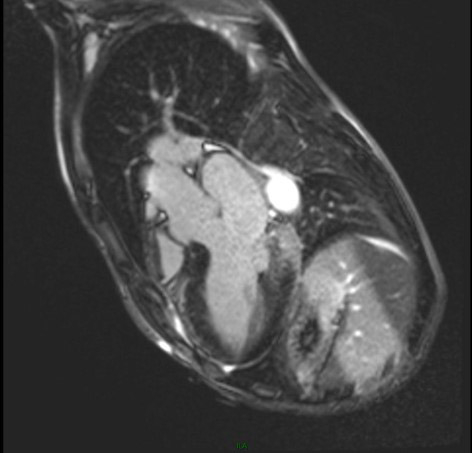

Résultats de l’IRM cardiaque:

- Fonctions systoliques bi-ventriculaires conservées avec dilatation tétra-cavitaire

- HVG concentrique (masse VG à 128 g/m2 pour une normale < 90 g/m2) avec épaisseur maximale à 15 mm en antéro-septo-basal (Figure 7)

- Hypertrophie VD avec épaisseur diastolique à 5 mm (Figure 8)

- Hypertrophie des piliers mitraux (Figure 9) et trabéculations bi-ventriculaires

Figures 7, 8 et 9 (de gauche à droite)

Figure 3 : Diminution de la relaxométrie T1 de façon diffuse avec valeur moyenne à 850 ms

Figure 4 : Relaxométries T2* normales: pas d’argument pour une hémochromatose

Figure 5a et 5b :Réhaussement tardif typique médiopariétal inféro-latéro-basal du VG = fibrose